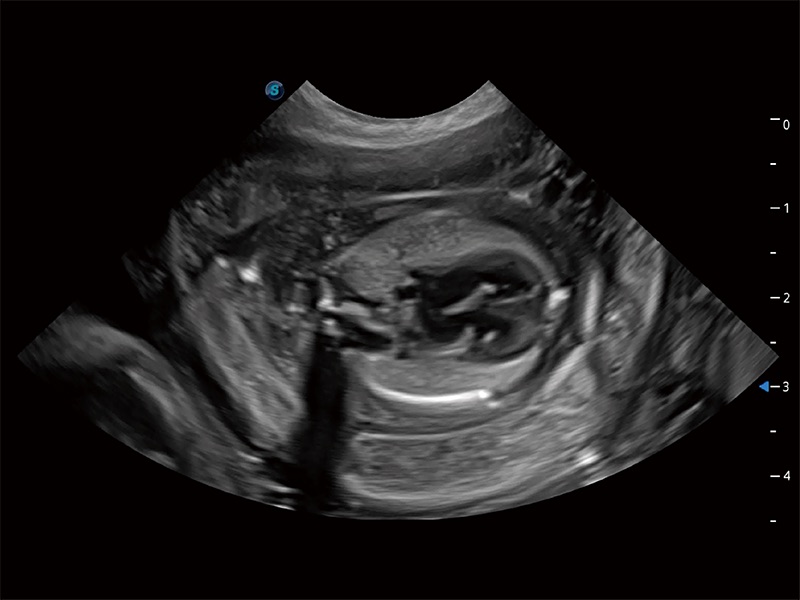

高性能和先進的臨床應用工具可以為動物醫(yī)生提供臨床信心。ProPet 80 搭載了先進的腹部和淺表應用工具,幫助醫(yī)生在日常臨床實踐中發(fā)揮前所未有的作用。

ProPet 80 專為動物醫(yī)生設計,對不同的動物體型和生理結(jié)構(gòu)作出了針對性的優(yōu)化。通過動物影像專用軟件,可滿足個性化的應用需求,幫助動物醫(yī)生獲得更精確的診斷數(shù)據(jù)。

ProPet 80 全新的動物超聲智能軟件和豐富的探頭群,為動物醫(yī)生提供了高清晰度和精細分辨率的圖像,無論在寵物、馬科、畜牧還是實驗室動物等應用中都可以輕松應對,為您的日常工作帶來滿意的體驗。